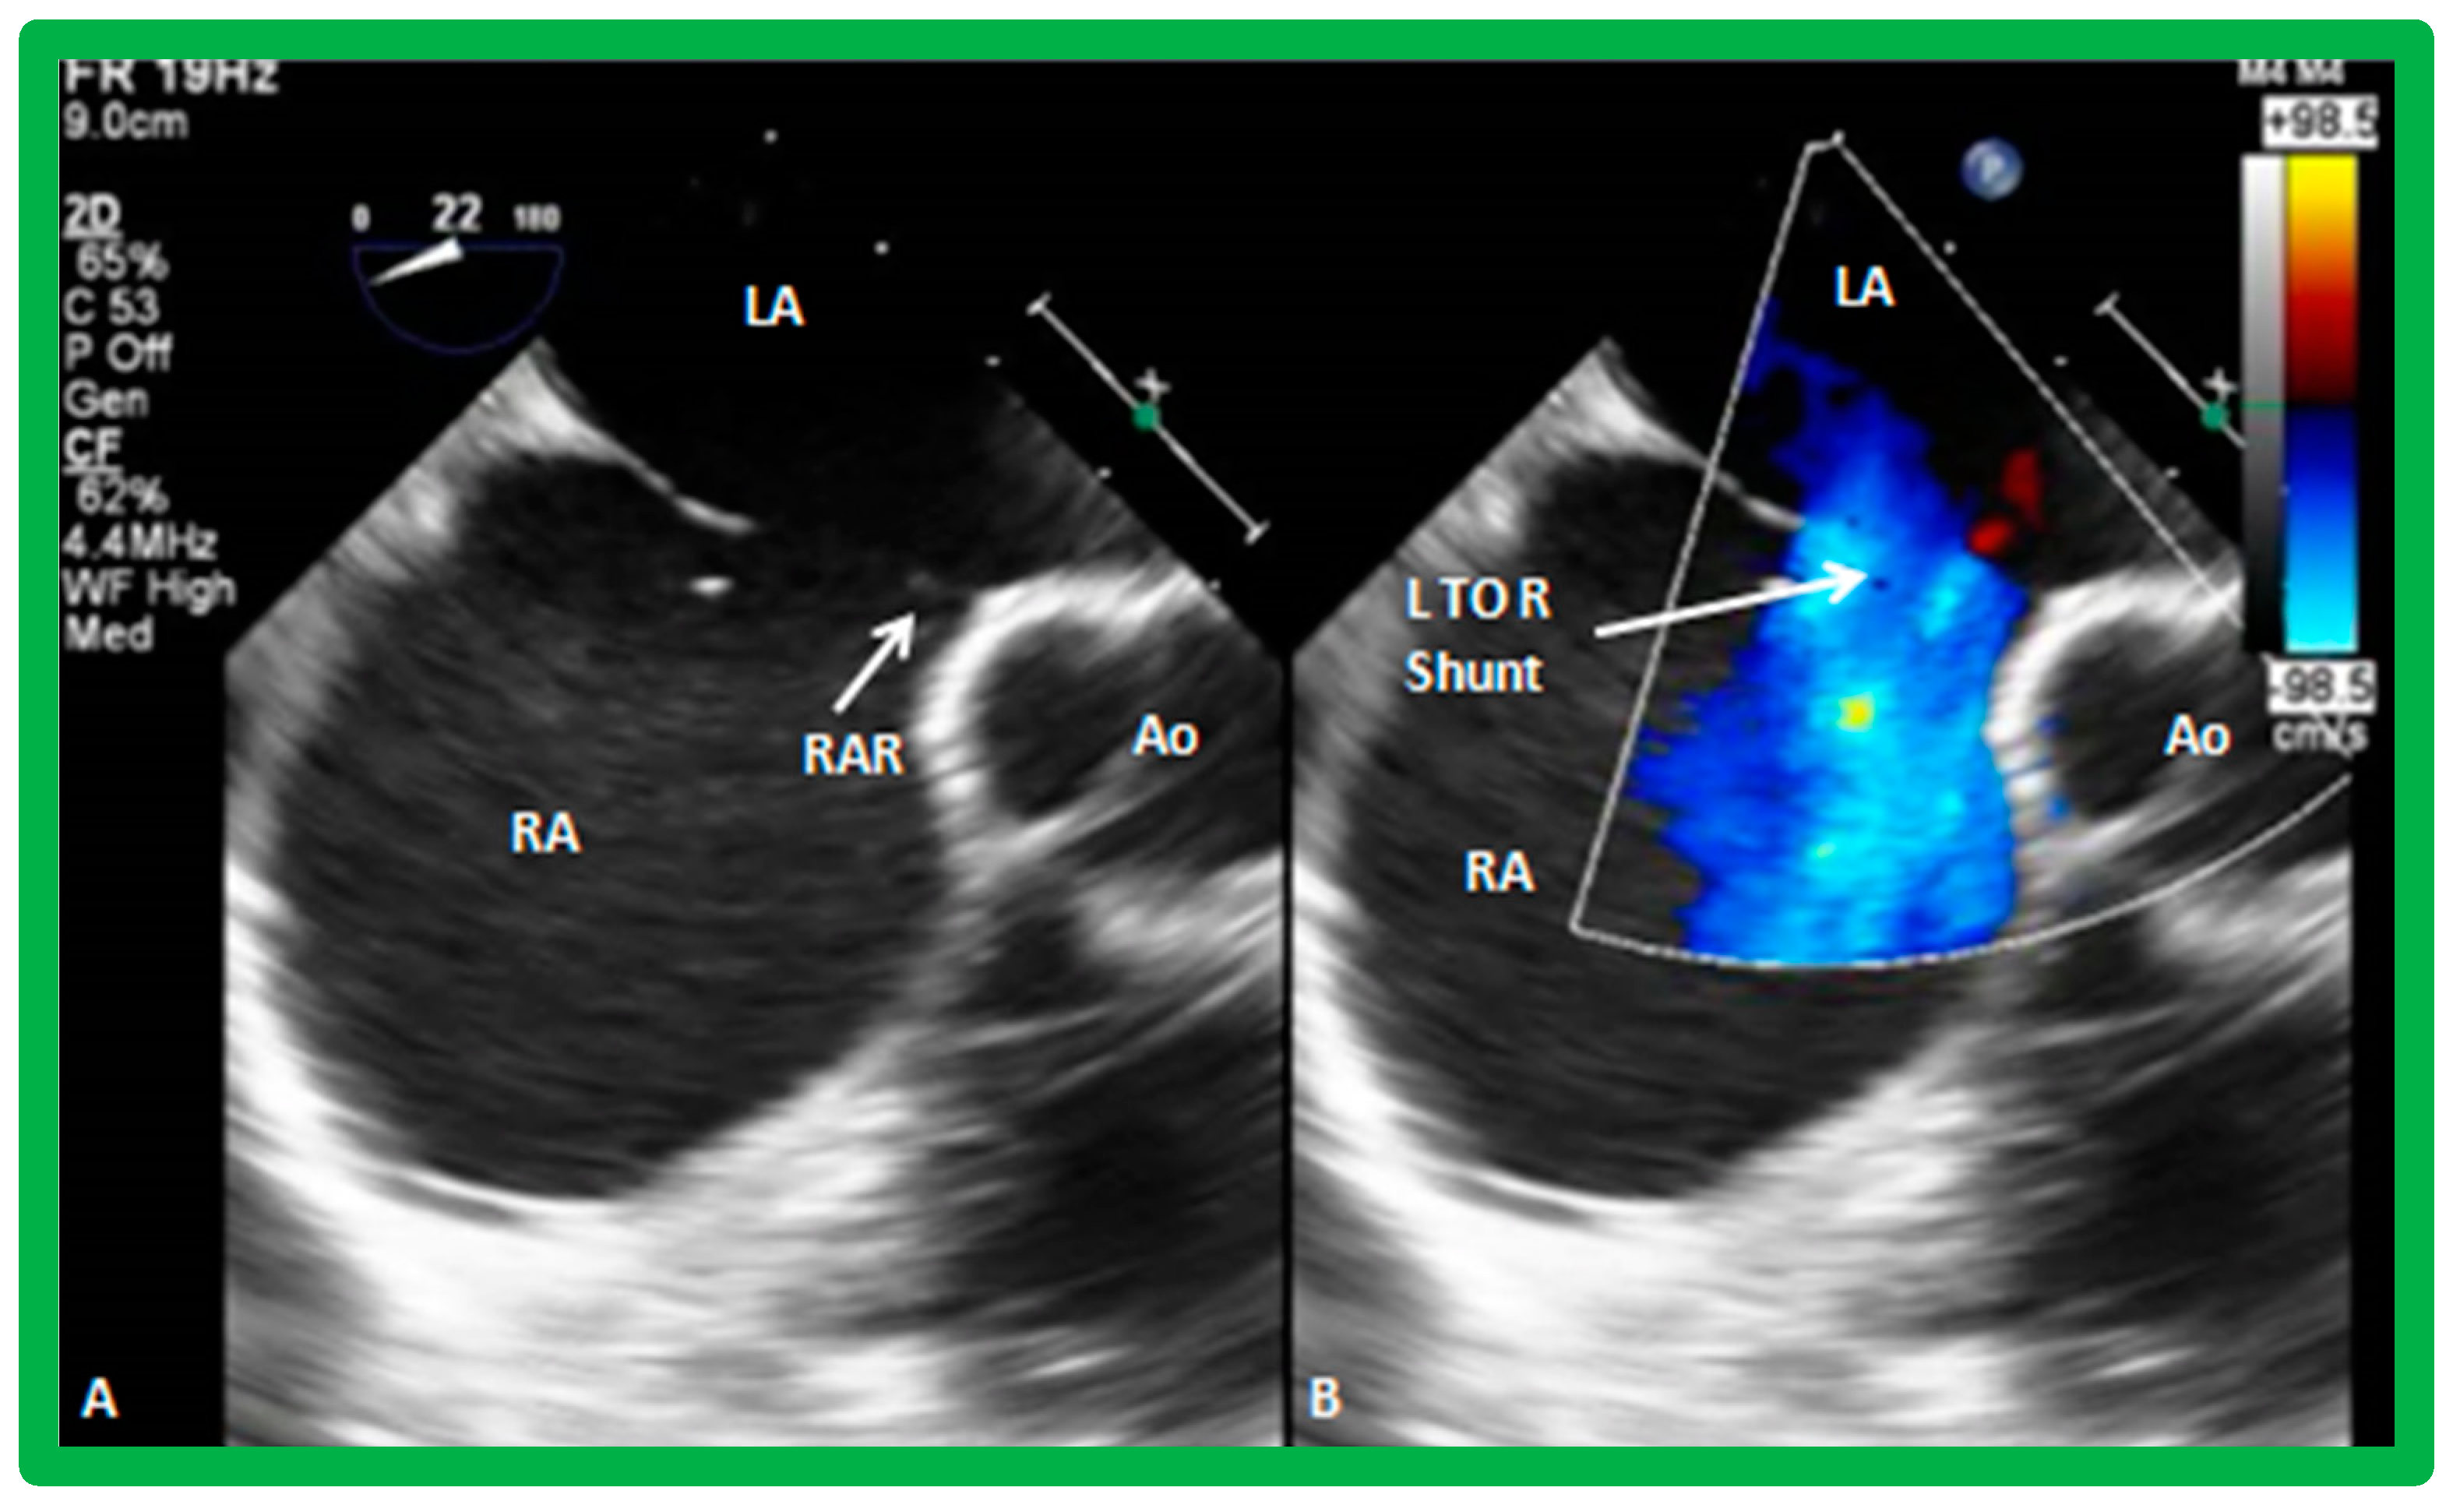

2. Diagnosis